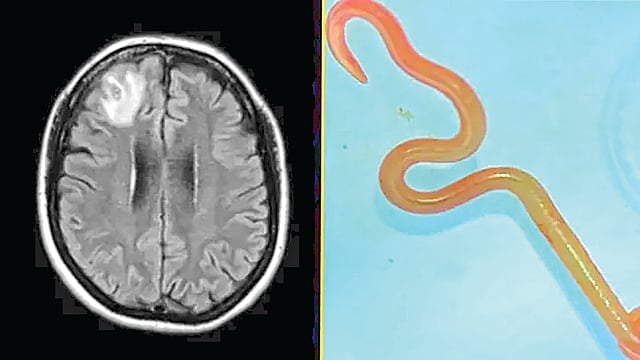

कॅनबेरा : ऑस्ट्रेलियातील न्यू साऊथ वेल्समधून एक अत्यंत दुर्मीळ आणि धक्कादायक वैद्यकीय घटना समोर आली आहे. एका 64 वर्षीय महिलेच्या मेंदूत डॉक्टरांना चक्क 3 इंच लांबीची एक जिवंत लाल गोलकृमी (Roundworm) सापडली आहे. गेल्या वर्षभरापासून ही महिला विविध आजारांशी झुंज देत होती, ज्याचे मूळ कारण शोधण्यात डॉक्टरांना मोठे यश आले आहे.

परदेश प्रवासाचा इतिहास असल्याने तिला जंतनाशक औषधेही देण्यात आली. परंतु, त्याचा काहीही उपयोग झाला नाही. सुमारे एक वर्षानंतर, महिलेला विस्मरण आणि नैराश्याचा त्रास होऊ लागला. डॉक्टरांनी जेव्हा तिच्या मेंदूचा एमआरआय केला, तेव्हा उजव्या बाजूला एक जखम दिसून आली. या जखमेची तपासणी करण्यासाठी जेव्हा शस्त्रक्रिया (Biopsy) करण्यात आली, तेव्हा डॉक्टरही चकित झाले. ‘शस्त्रक्रियेदरम्यान मेंदूत एक दोरीसारखी रचना दिसली, जो प्रत्यक्षात 3 इंच लांब आणि 1 मि.मी. जाड असलेला एक जिवंत लाल रंगाची परजीवी कृमी (Helminth) होता.’

शस्त्रक्रियेद्वारे ती कृमी बाहेर काढल्यानंतर महिलेवर विशेष औषधोपचार करण्यात आले. तसेच, आयव्हरमेक्टिन आणि अल्बेंडाझोल यांसारख्या जंतनाशक औषधांचा डोस देण्यात आला. शस्त्रक्रियेच्या सहा महिन्यांनंतर महिलेच्या फुफ्फुसातील आणि यकृतातील जखमा पूर्णपणे बर्‍या झाल्या असून, तिची मानसिक प्रकृतीही सुधारली आहे. ही घटना वैद्यकीय क्षेत्रासाठी एक मोठा धडा मानली जात आहे. कारण, हा विशिष्ट प्रकारचा परजीवी मानवी मेंदूत सापडण्याची ही पहिलीच वेळ असावी.